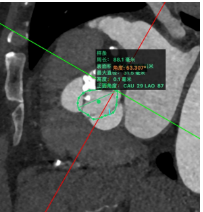

主动脉CT

原生物瓣形态:最大直径18.3mm;

冠脉风险尚可;冠脉切线面窦宽30mm,冠脉距离生物瓣距离>4mm,风险可控;

入路情况:升主有扩张,直径46mm,胸主腹主动脉无明显迂曲,双侧股动脉入路较好,右股可作为主入路;

考虑植入深度:生物瓣缝合环下5mm。